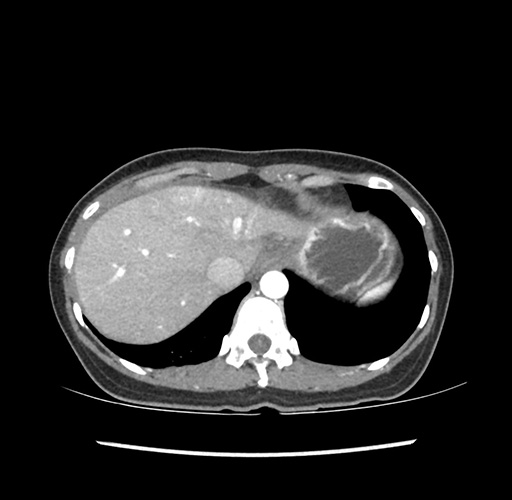

Imaging Analysis

Look through the patient's CT scan to identify any areas of concern for the necessary procedure.

Based on your CT findings, which issue(s) would give reason for "planned slowing down moment(s)" in this case?

Considering a standard left lateral sectionectomy procedure, what step(s) of the operation would you do differently in this case ?